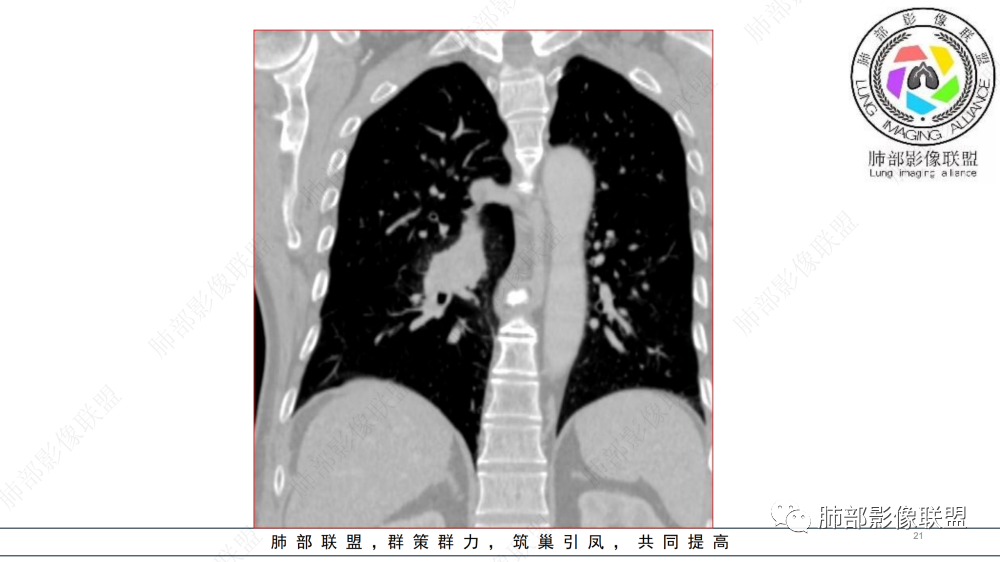

晨读 右肺中间段支气管至下叶支气管狹窄,腔内见软组织肿块,腔内外侵犯,右下肺门软组织肿块形成,不均匀强化,冠状位病变纵径大于横径,远侧肺内阻塞性炎症。定性恶性,考虑腺样囊腺癌或鳞癌

右肺下叶肺门区肿块,向中间段支气管突出,下叶支气管阻塞狭窄,腔内外侵犯,不均匀强化,内可见低密度,冠状位病变沿支气管走行生长,远侧肺内阻塞性炎症,考虑鳞癌,鉴别类癌

晨读:男,57,咳嗽半年,痰中带血3天。胸部CT:右中间段支气管到下叶支气管堵塞性狭窄,管腔内见软组织肿块,壁内外侵犯,长轴沿气道延展,下叶基底多段累及,病变纵径大于横径,远侧可见索条、阻塞性炎症。考虑恶性,腺样囊腺癌?鳞?鉴别N内分泌类、炎性肉芽肿等